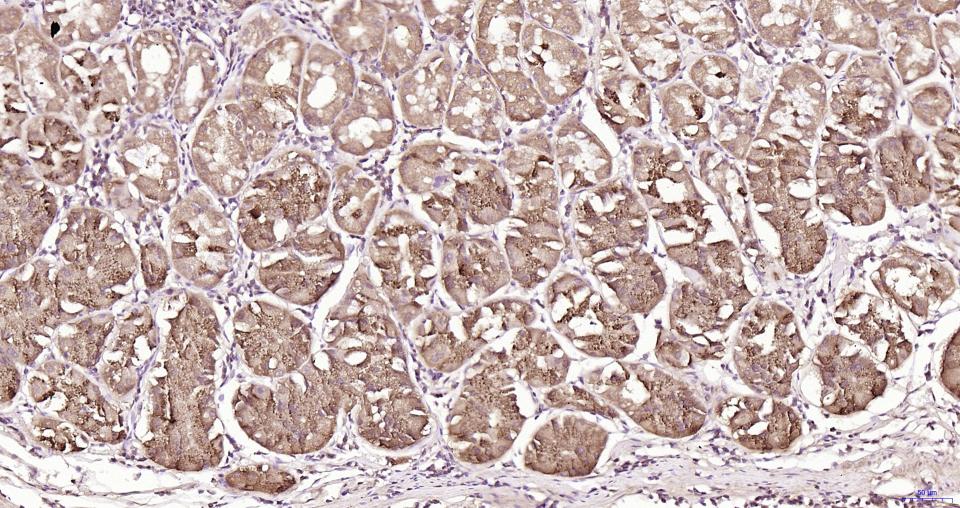

Paraformaldehyde-fixed, paraffin embedded Human Liver; Antigen retrieval by boiling in sodium citrate buffer (pH6.0) for 15 min; Antibody incubation with MyD88 Monoclonal Antibody, Unconjugated(bsm-61269R) at 1:200 overnight at 4°C, followed by conjugation to the SP Kit(Rabbit, SP-0023) and DAB (C-0010) staining.